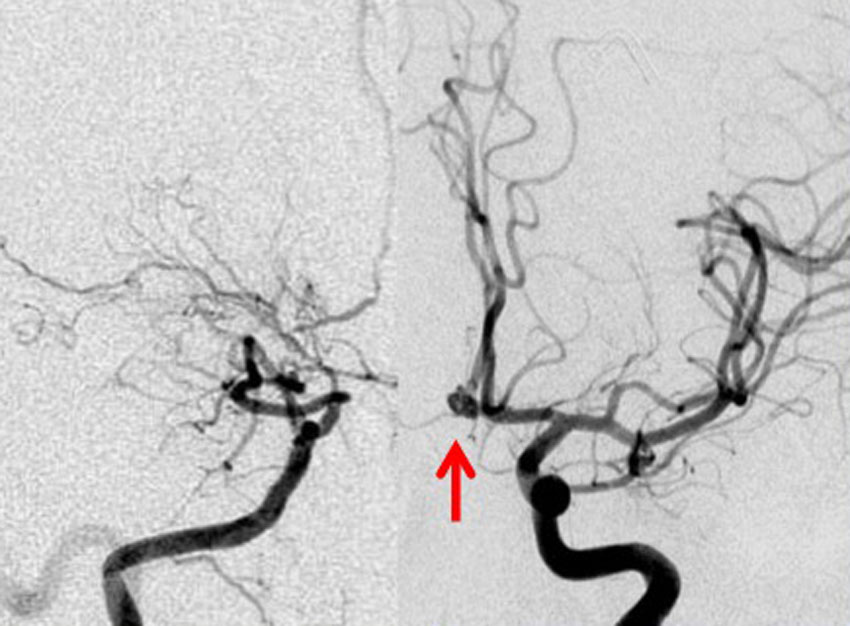

4歳の時に頭蓋咽頭腫に対して50グレイの分割照射を受けました。両側の内頸動脈と前交通動脈が被曝しています。16歳(12年後)に左片麻痺の虚血発作を生じました。右内頸動脈が閉塞してウィルス動脈輪閉塞(モヤモヤ病)になっていました。前交通動脈に動脈瘤(赤矢印)もできていました。小児の頭蓋咽頭腫への放射線治療ではかなり高率に閉塞性脳血管障害を生じるのですが,治療後10年以上がたってから起るので,治療を行った医師はそれをみることはほとんどありません。